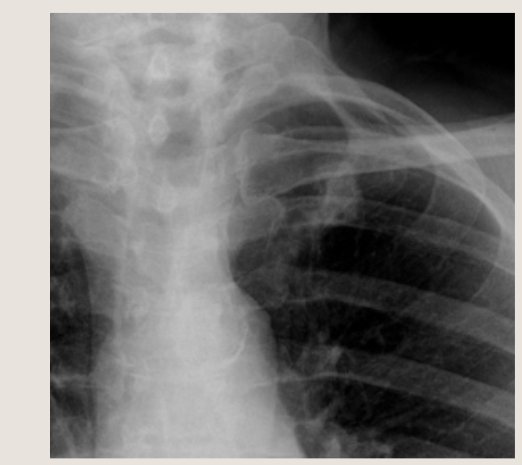

左肺尖部、あやしいかな。

肋骨の断端かな? 結節影?

結局CT撮るんですよ。呼吸器内科の先生だって結局CT撮るんですよ。だったら、今日内科でCT撮ったほうがいいでしょう。何もなければ今日で終了です。あやしい影があったら、読影に出して(呼吸器内科の先生も読影があったほうがうれしいでしょう)呼吸器内科外来を予約してあげましょう。